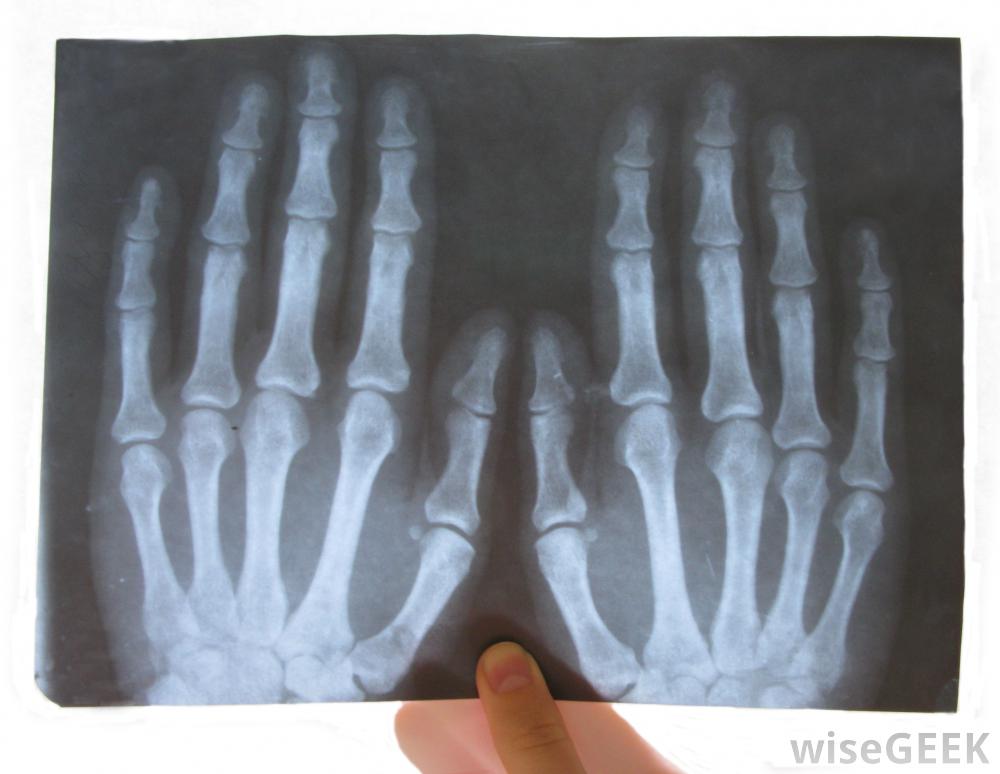

在腕掌關節置換術前,外科醫生可以對手進行物理檢查,并復查x光片,以了解損傷的具體性質這使得外科醫生可以制定一個計劃,包括剃掉多余的骨頭,移動肌腱或韌帶,或在拇指中植入材料來穩定關節。最佳選擇不光取決于具體情況,但患者的病史和術后希望恢復的活動水平。